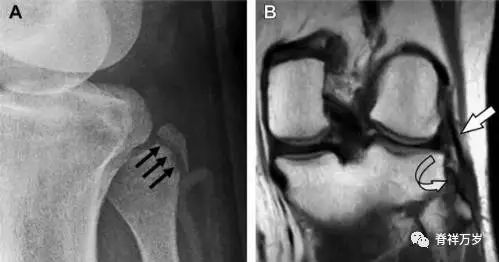

11Segond 骨折

Segond 骨折是发生在胫骨平台外侧的垂直撕脱性骨折(图 4)。这种骨折在前后位 X 线片上显示最佳。

屈曲位时膝关节受到内旋*力暴**作用,导致皮质骨撕脱性骨折,这种骨折常发生在运动员身上。常引起股骨内髁和胫骨平台后内侧骨挫伤,75%~100% 的患者伴前交叉韧带断裂,33% 的患者伴外侧半月板损伤。

图 4 一位足球运动员的 Segond 骨折

A 正位片示关节线下方胫骨外侧皮质撕脱(箭头)。B MRI 冠状位 T1 加权像示附着于髂胫带的骨折碎片(空箭头)。

12反向 Segond 骨折

胫骨平台内侧皮质骨撕脱性骨折,被称为内侧 Segond 骨折或反向 Segond 骨折(图 5)。这种骨折的旋转机制与 Segond 骨折相反,该骨折与后交叉韧带断裂及内侧半月板损伤相关。

图 5 一位足球运动员的反向 Segond 骨折

A 正位片示关节线处的胫骨内侧见一细小骨折片(箭头)。B MRI 冠状位 T1 加权像示骨折片出现在内侧副韧带关节囊附着处(方框)。